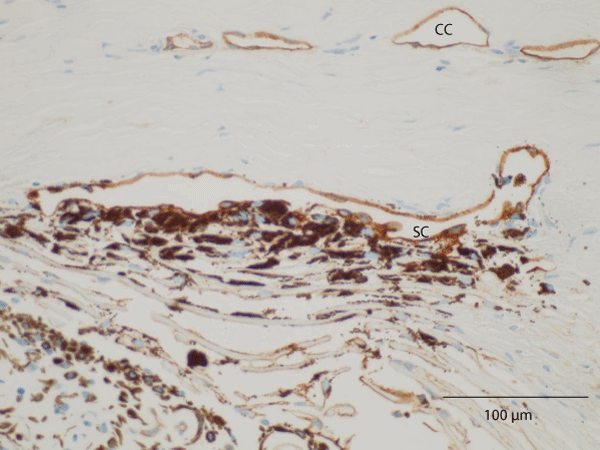

| CC: Collector Channels |

| Figure 4: Light microscopic photograph of a specimen subjected to thrombomodulin immunohistochemical staining, which can be used to detect Schlemm’s canal (SC). Trabecular cells in the uveal and corneoscleral meshwork were heavily pigmented. The most conspicuous finding was the existence of strongly pigmented trabecular cells in the cribriform meshwork. Note the absence of trabecular lamellae fusion and the normal size of the SC, which was positively stained with thrombomodulin |